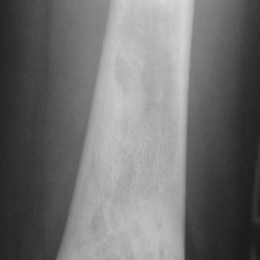

Radiographic imaging is used to help form a diagnosis. These include X-Ray, MRI, CT and Bone Scans.

An example of a X-Ray is shown.